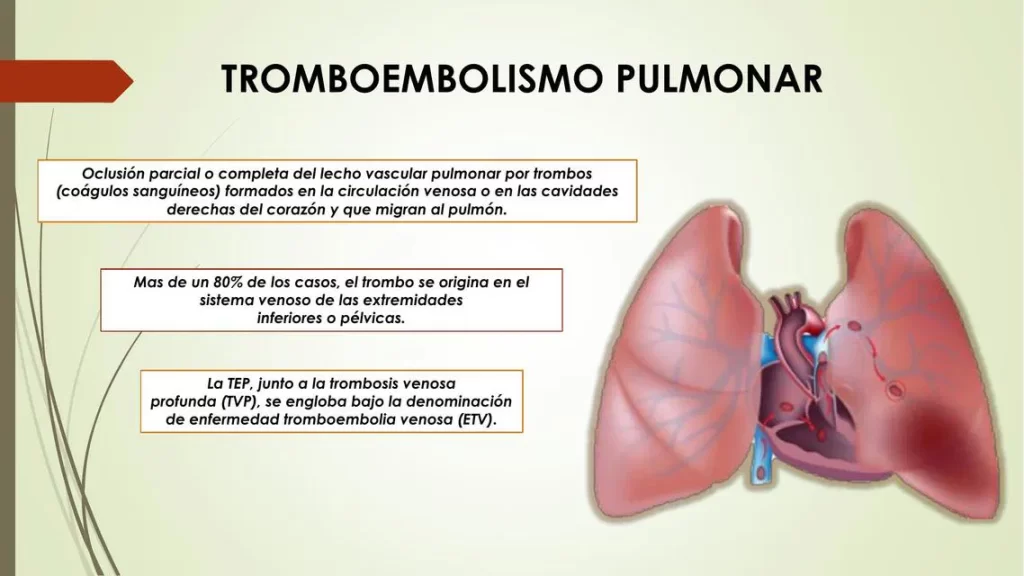

O Tromboembolismo Pulmonar (TEP) é uma condição grave caracterizada pela obstrução de uma parte das artérias pulmonares por um coágulo de sangue. Este coágulo geralmente se desloca de outra parte do corpo, sendo as pernas o local mais comum.

O TEP impede o processo fundamental de oxigenação do sangue:

- O coração bombeia sangue pobre em oxigênio para os pulmões.

- Devido à obstrução do coágulo, esse sangue não consegue chegar para ser oxigenado.

- A obstrução leva a um aumento da pressão sanguínea (hipertensão pulmonar).

- O aumento da pressão sobrecarrega e enfraquece o ventrículo direito do coração.

- Consequentemente, órgãos e tecidos vitais não recebem o sangue oxigenado necessário para funcionar corretamente.